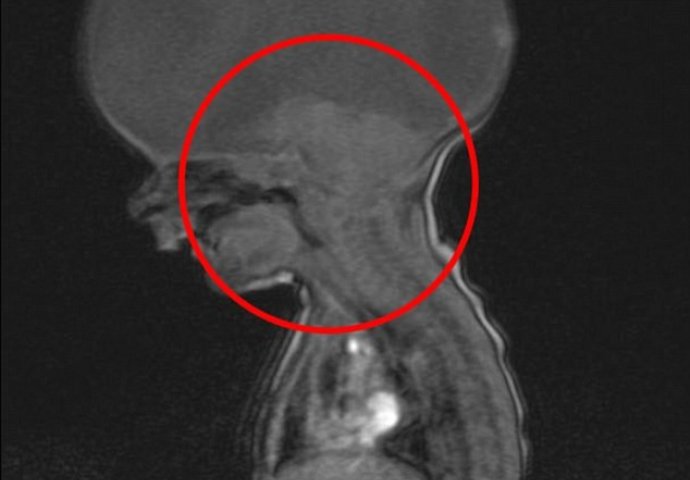

Holoprosencefalija, rijetka bolest koja uzrokuje prestanak razvitka mozga tokom razvoja bebe u stomaku. Rendgenski i drugi snimci pokazivali su da se bebin mozak neće razvijati u skladu s vremenom.

Samo je moždano stablo bilo razvijeno, što je značilo da može da reguliše disanje i ostale fiziološke funkcije. Praznina u dječakovoj glavi bila je ispunjena tečnostima.